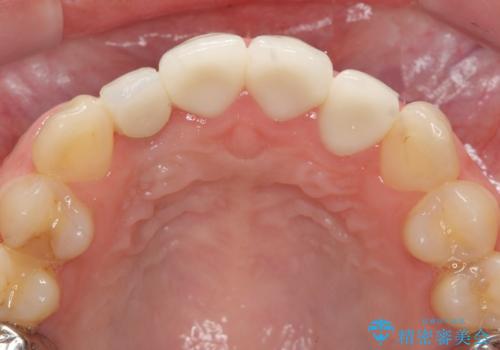

充填されたコンポジットレジン・再発した虫歯を神経に影響が出ないよう丁寧に除去し再充填をしたのちオールセラミッククラウンで前歯の審美性を回復します。

- 33万円(仮歯・ジルコニアクラウン×3)費用は治療当時の料金となります